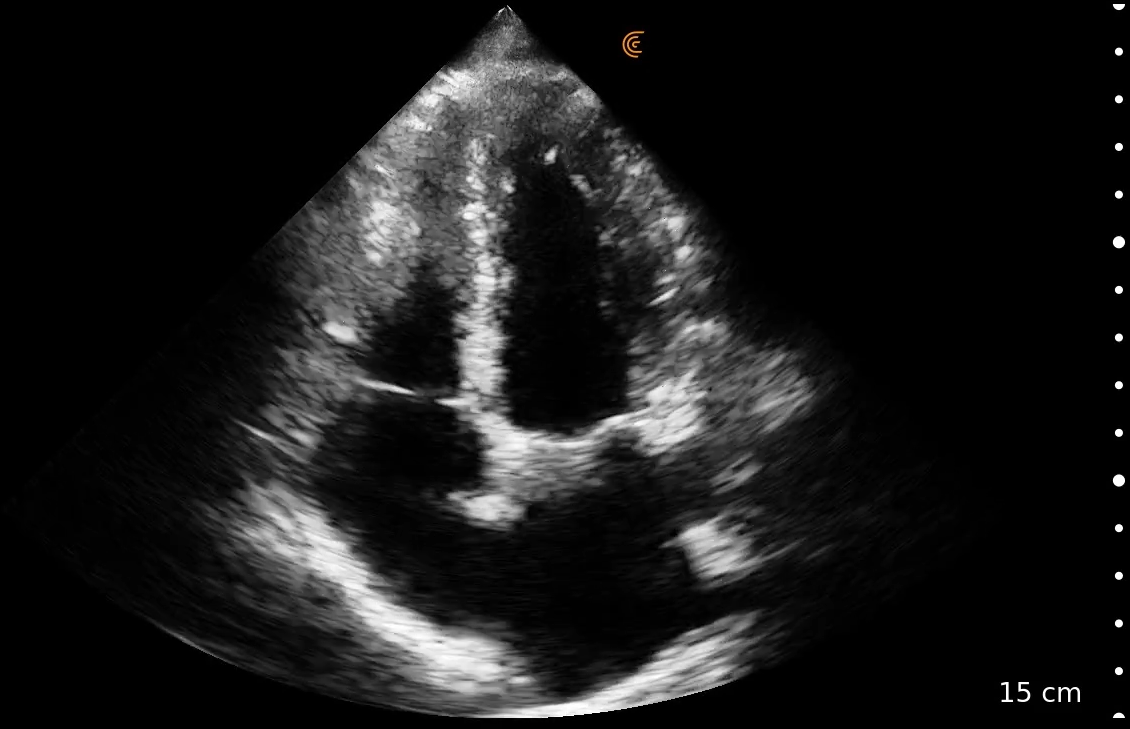

Singurul ecograf wireless de buzunar care oferă o imagine nealterată, comparabilă cu sistemele tradiționale de top. Utilizează o rețea securizată WifiDirect pentru conexiunea cu aplicația de pe multiple dispozitive de vizualizare simultan.

Sondă phased array cu domeniul de frecvență între 1-5 Mhz, adâncimea de scanare reglabilă între 3-40 cm. Moduri de lucru disponibile: B, M, PW, CDFI și Power Doppler. Pachete de măsurători incluse: Cardiac, Abdomen, OB/GYN, Vezică, Plămân, Superficial.

IDEAL PENTRU: Acces abdominal, cardiac, pulmonar, vascular

- Imagini de calitate superioara, comparative cu cele de pe ecografele stationare avansate